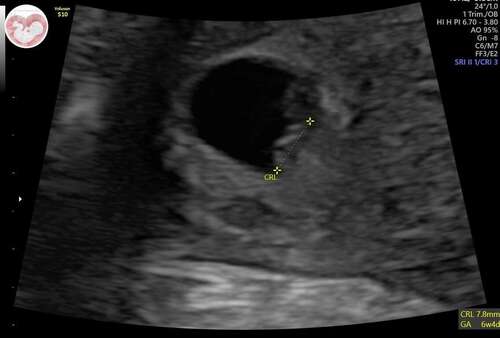

Echo 26/10/2023 - 5+6 weken zwanger volgende week maandag 06/11/2023 nieuwe echo 7+3 weken dan zwanger